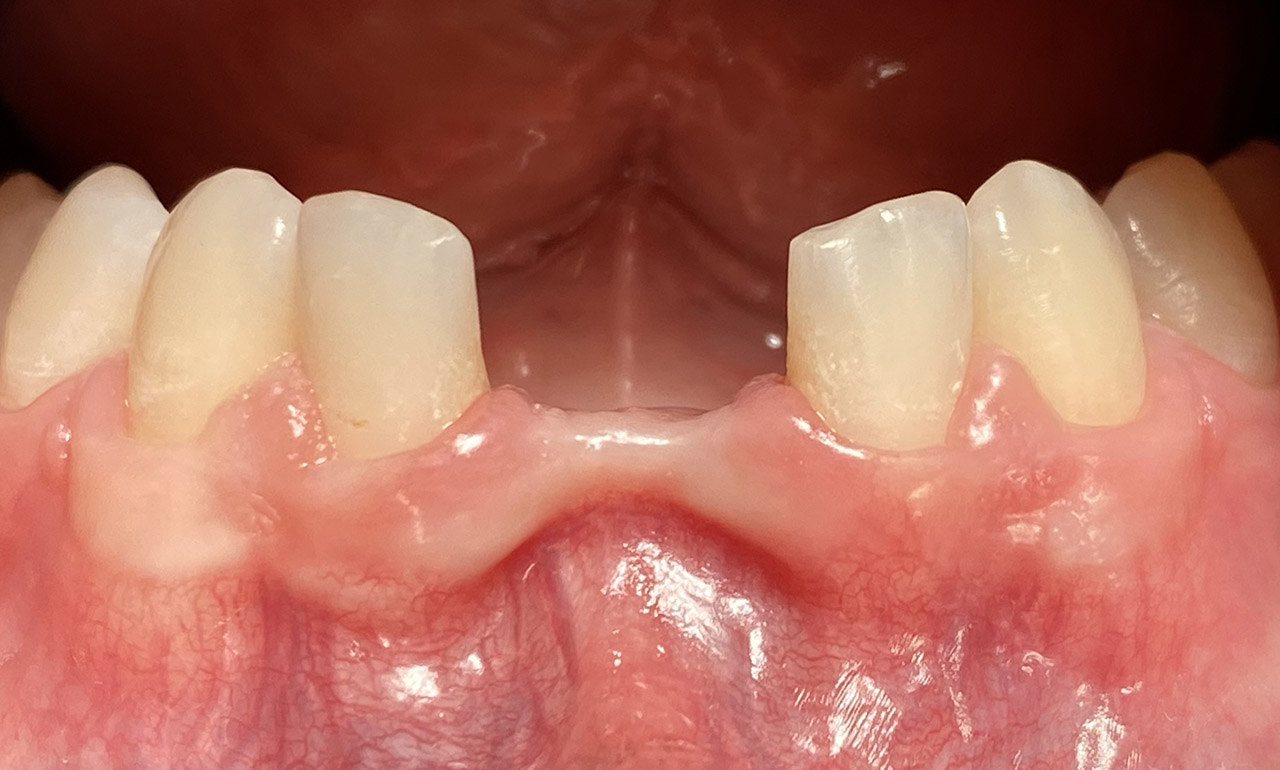

Prophylaxe/professionelle Zahnreinigung:

Zur Motivation, Information und Instruktion einfärben der Beläge (bakterieller Biofilm) bei jungem Patienten in kieferorthopädischer Behandlung. Reinigung der Zähne mit Pulverstrahltechnik minimalinvasiv und zahnschonend und wo noch nötig gezielt mit Ultraschall.

Das Resultat 45 Minuten später.